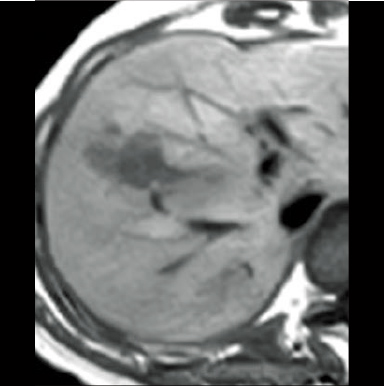

2D-RSSG Dynamic EOB